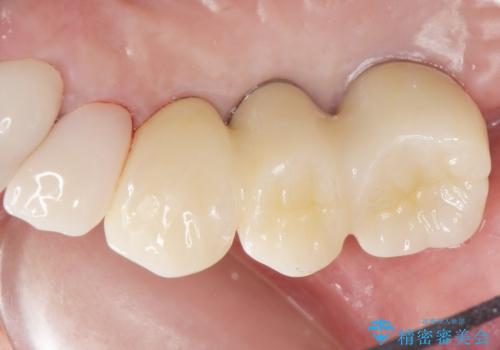

しっかりと咬むことができるようになり、喜んで頂けました。

他院ではお断りされたインプラント治療を行うことができ、ご満足頂けました。

インプラントの種類:ストローマン BLT

被せ物の種類:オールセラミッククラウン ベレッツァ